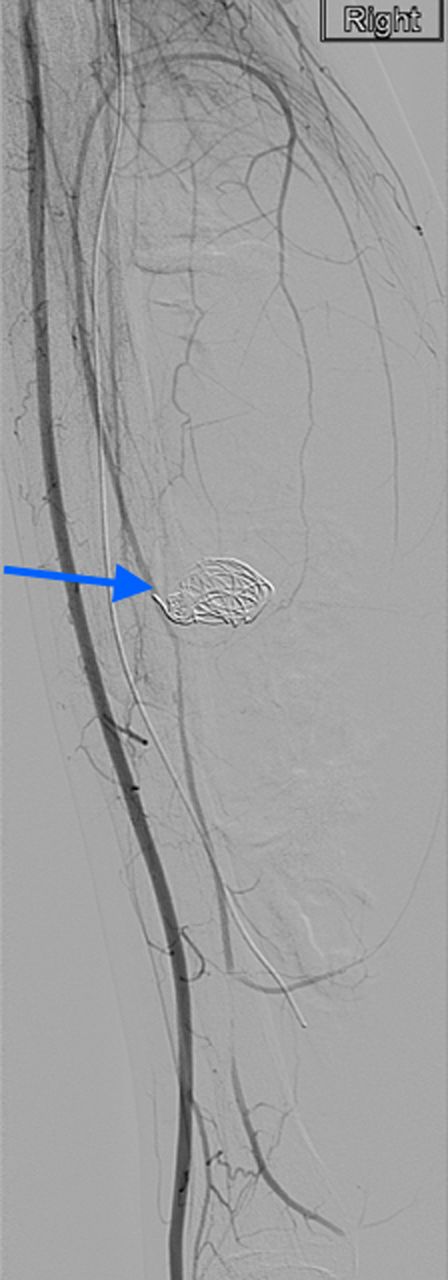

A 20-year-old man with no past medical history presented to the emergency department with non-displaced and closed transverse fracture of the left mid-tibial shaft and an intact fibula induced by a tackle during a football match. On examination, he had no neurovascular deficit and all crural pulses were palpable. His fracture was treated conservatively with a non-weight bearing above knee plaster cast later replaced by a below knee cast for a total period of 6 months. Upon examination during his attendance to the facture clinic, x-ray demonstrated no signs of fracture union. The subsequent magnetic resonance imagining (MRI) confirmed a nonunion of the fracture along with an ovoid 2.7 cm posterior compartment vascularized mass causing bowing of the interosseous septum with no evidence of avascularity of the bony margins (Fig. 1). This was confirmed to be a pseudoaneurysm originating from the PTA. An endovascular approach was adopted, and the pseudoaneurysm was injected with 2 ml of thrombin, filled with multiple coils and deployment of an angiography balloon (in the sac) (4 mm × 6 cm) for 7 min (Fig. 2). This resulted in complete cessation of the pseudoaneurysm with normal flow in the PTA (Fig. 3). The residual extravasated hematoma was later drained by an open approach. Follow-up x-ray (6 months) demonstrated complete union of the fracture site with no associated complications.

Complete resolution of the pseudoaneurysm and confirmed patent PTA.